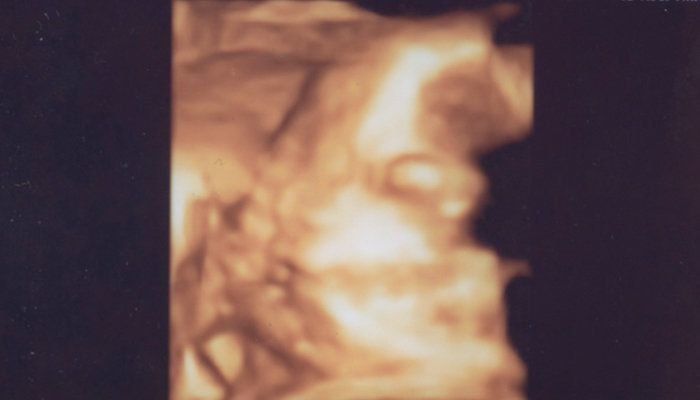

Chisatoさんの妊娠38週目のエコー写真 間もなく生まれる

推定体重2918g。妊娠36週を迎えてからは、検診が週1回になり、おなかにセンサーを貼って胎児の心拍を調べるNST検査が行われます。この日は確か「少しおなかの張っているタイミングがありますね~」と言われました。そして、この日の4日後に出産となるのでした。